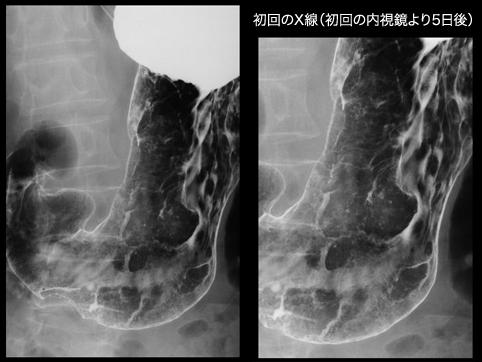

疾病(病理主体)的分类炎症性・溃疡性疾患/其他

部位(按器官分)胃(部位)/2个以上

检查方法X线

肿瘤最大直径30~34